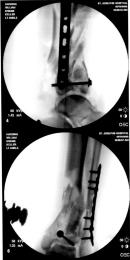

X-Rays and scans of the damaged right & left legs plus the pelvis

These x-rays were taken just after the accident. Some of the bones on the right leg have already been pushed back into the leg. The CT

scans show various views of the ankles and pelvis prior to any corrective surgery. Fibula bracing is clear in some of the images as well as

bracing that was used to secure the "open book" pelvis. In some of the last images it is apparent that the upper part of Liam’s left fibula is

broken. Liam was told that the pain he felt was most likely a muscle cramp. Nothing was done to repair this break and you will see in further

x-rays that the bone shifted and later fused in such a way as to add to the reduction of Liam’s leg length. The last photo shows the stint

used to block any potential blood clots from moving up.

Pre-corrective surgery X-Rays of the damaged right & left legs / ankles

These x-rays were taken at Dr Armendariz’s office, just prior to performing any corrective surgery. As can be seen in these images,

there was no tibia bracing provided by Dr. Keller. Liam was released from Dr Keller’s care with instructions that full weight bearing could

be accomplished within 2 months of Keller’s last surgical procedure. The best example to examine is the second image (from the left) of the

top how. Notice how the bones that should be aligned with the tibia are in fact on the other side of the leg. The third image shows how badly

Liam’s left foot was twisted as a result of the pool placement of the external fixation. What is not obvious is that the screw at the bottom

of the plate on the right fibula missed being screwed into the plate.